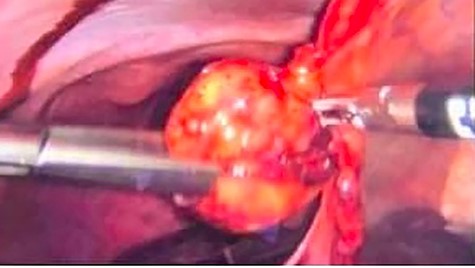

Due to extreme pain of the patient laparoscopic exploration was performed and laparoscopic excision of the twisted lipoma, which was hanging from the ligamentum teres hepatis, followed (Fig. 2). Postoperative period was normal, and the patient was discharged a day after her surgery in very good condition. Final pathological examination reported a CD68 (+) adipose tissue with fibrous septa and inflammatory cells. CD68 is a glycoprotein that is highly expressed in macrophages. Diagnosis of torsion lipoma was histologically confirmed.